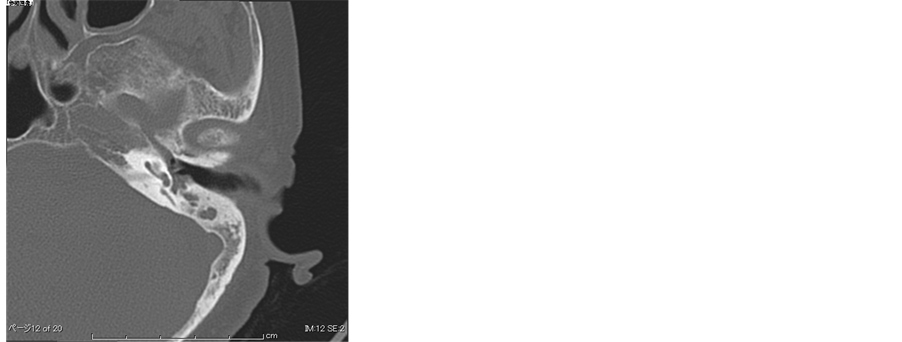

Case 2. A 65-year-old female was referred to our hospital for the investigation on progressive bilateral sensorineural hearing loss. She had been diagnosed with bilateral COM 12 years previously and she had been suffering from ear discharge. She had also been treated with oral steroid therapy for bronchial asthma. She was also diagnosed with chronic sinusitis with nasal polyposis. The middle ear viscous discharge contained numerous eosinophils and she was diagnosed with EOM according to the 2011 diagnostic criteria [6] . Temporal bone CT showed low density areas in the mastoid and tympanic cavities but MRI showed no ossification of the cochlea (Figure 4(a), Figure 4(b)). In spite of anti-IgE therapy in combination with oral steroids, an anti-histaminergic agent and leukotriene receptor antagonist administration, her hearing threshold was gradually deteriorated, and she developed bilateral profound hearing loss at the age of 70 (Figure 5). Her speech recognition score was 20% (Japanese monosyllable list) in both ears. As the middle ear discharge was persistent, we decided not to perform the cochlear implant at that time. 3 years later, she insisted on receiving a cochlear implant since she could not hear at all with hearing aids. The electrode array (Med-EL Flex28) was inserted into the scala vestibule in her left ear as ossification of the scala tympani was found during the surgery. Myringoplasty was also performed in her left ear. No complications in relation to the implant device or skin flap were observed during a two-year follow- up. In spite of postoperative oral steroid administration, the tympanic membrane was re-perforated and ear discharge recurred three months post-surgery (Figure 6). Her speech recognition score was 20% (Japanese monosyllable list).

Figure 4. (a) Preoperative CT of Case 2. Low density area in mastoid and tympanic cavity; (b) Preoperative 3D MRI of Case 2. Ossified cochlea was not evident.